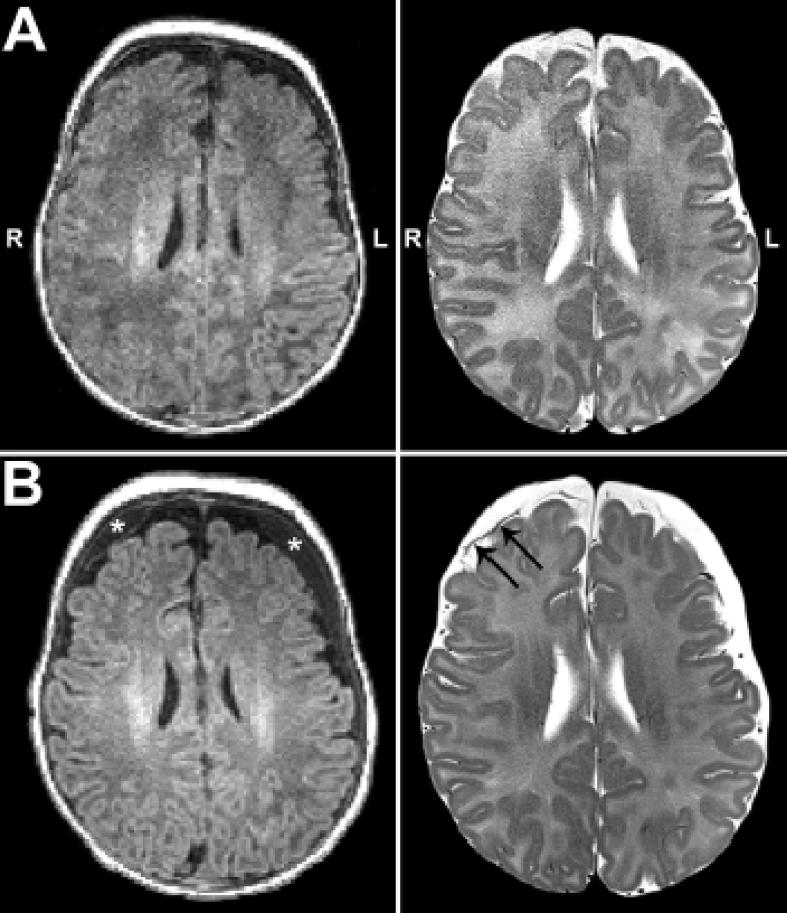

We report the case of a former 33-week premature infant born with long-gap esophageal atresia that underwent complex perioperative critical care (Foker process) requiring prolonged post-operative sedation and whom presented with incidental subdural hematoma. Rs-fMRI data was acquired (at 1-month corrected age) and (at 2.25-months corrected age) complex perioperative care. We evaluated resting-state functional connectivity (RSFC) using graph theory to explore the complex structure of brain networks.

A transient increase in head circumference coincided temporally with lifting of sedation and initiation of sedation drugs weaning, and qualified for hydrocephalus (93%) but not macrocephaly (>95%). RSFC analysis identified networks spatially consistent with those previously described in the literature, with notable pre-post-treatment qualitative differences in correlated and anticorrelated spontaneous brain activity.

头围的短暂增加在时间上与镇静解除和镇静药物减量开始相吻合,符合脑积水标准(93%)但不符合巨头症标准(>95%)。RSFC分析确定的网络在空间上与先前文献中描述的网络一致,治疗前后相关和反相关的自发脑活动存在显著的定性差异。